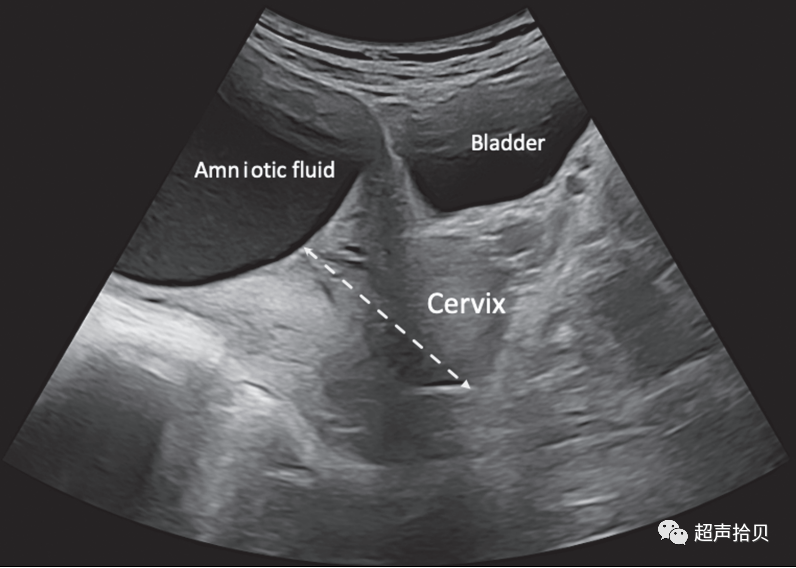

胎盘

建议

• 应检查胎盘与宫颈内口的关系良好实践证据

• 如果经阴道超声检查胎盘下缘与内口之间的距离≤15 mm,建议在妊娠晚期进行随访检查(推荐等级:C)

• 如果在常规妊娠中期扫描中怀疑胎盘植入,建议进行更详细的评估良好实践证据)。

1. 应评估和描述胎盘位置(图 7 )、其与宫颈内口的关系(通常使用经腹超声)以及图像特征。胎盘异常表现的例子包括出血、三倍体中的多个无回声囊肿(与正常腔隙不同)和胎盘肿块,如绒毛膜血管瘤。

2. 在大多数情况下,在常规的妊娠中期检查中,经腹超声检查可以清楚地确定胎盘和宫颈内口之间的关系。如果胎盘下缘到达或重叠内口,建议在妊娠晚期进行随访检查.

3. 尽管几乎没有证据表明重新评估低置胎盘的最佳截止值,最近建议使用妊娠中期扫描时的经阴道成像,前部和后部胎盘的可能胎盘迁移的截止值分别为距内口 5 毫米和 15.5 毫米。孕期低位胎盘“迁移”(即胎盘边缘和内口之间的子宫壁生长)很常见,在大多数情况下,妊娠晚期的随访将确认胎盘位置正常.

胎儿mt是什么检查什么疼吗【文献学习】【规范、指南】ISUOG实践指南:中孕期胎儿常规超声检查(2022更新)_https://www.jmylbn.com_新闻资讯_第24张

图7胎盘位置应根据母体宫颈确定(虚线箭头)。